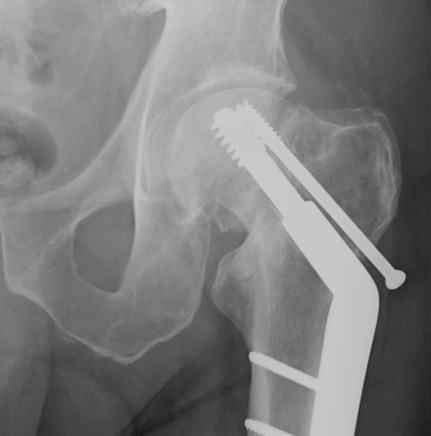

Sliding hip screw (SHS/DHS) + derotation screw

DHS and derotation screw

Youtube step by step sawbone guide